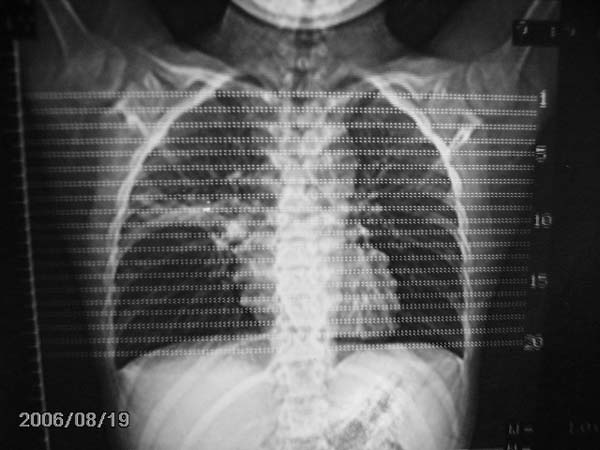

男,13岁,发烧半月,干咳无痰,正规使用抗生素半月,现在仍是午后低烧!!!未做痰检

结合临床考虑:右肺中叶结核可能性大.

右肺中叶结核可能性大

右肺结核,右肺中叶不张

右侧肺门淋巴结好象有增大,会不会是个原发综合症合并感染

右肺中叶大片状密度增高影,内密度不均匀,右肺门处增大,应该是淋巴结肿大,结合临床首先考虑原发性肺结合可能性大,不排除合并感染可能,建议治疗后复查.

灶内密度不均,似乎有囊状,条状影,考虑右中叶综合症; 从照片中看不出有无钙化灶,若明显则考虑结核性。

考虑中叶综合征(右肺门肿大淋巴结伴中叶阻塞性炎症)